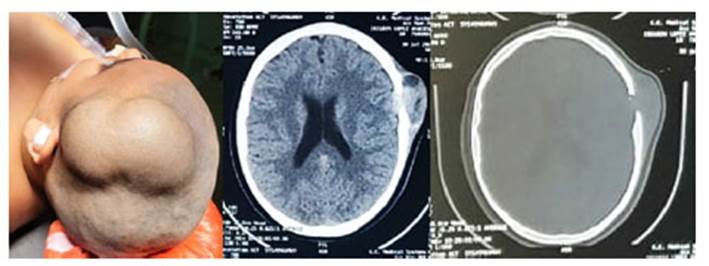

Varón de 10 años de edad, sin antecedentes de importancia, con un tiempo de enfermedad de 4 semanas, con un tumor en la región parietal izquierda, de crecimiento rápido, doloroso y de consistencia blanda. Se refiere que el paciente sufrió un golpe jugando con su hermano, y que fueron los padres quienes se percataron de la lesión. Los estudios de imágenes con TAC, informan una única lesión quística bilobulada con erosión de cráneo y con comunicación intracraneal a duramadre (Figura 1). El paciente fue sometido a una cirugía; donde se halló una lesión quística con área de clivaje, muy vascularizada con infiltración de tejido celular subcutáneo (TCSC), músculo temporal, hueso de cráneo y duramadre, haciendo una resección en bloque, con ruptura de quiste (Figura 2). En el estudio de patología se evidenció macroscópicamente una lesión quística de 12cm de longitud, con restos de coágulos y una pared de 0,6 cm; a la microscopía, se observaron células grandes con escaso citoplasma, núcleos irregulares, con hendidura nuclear, y micronucléolos, acompañado de abundantes eosinófilos, que comprometen el TCSC, músculo, hueso parietal, duramadre, sin infiltración de parénquima cerebral. CD1A Y S100 y BRAF positivos (Figura 3). Actualmente se encuentra asintomático y en estudios de extensión.

Figura 1 TAC; única lesión quística bilobulada con erosión de cráneo con comunicación intracraneal a duramadre.

Figura 2 Vista externa. B. Vista interna. Se muestra lesión quística (A y B) con área de clivaje, muy vascularizada con infiltración de tejido celular sub cutáneo, musculo temporal, hueso de cráneo y duramadre.